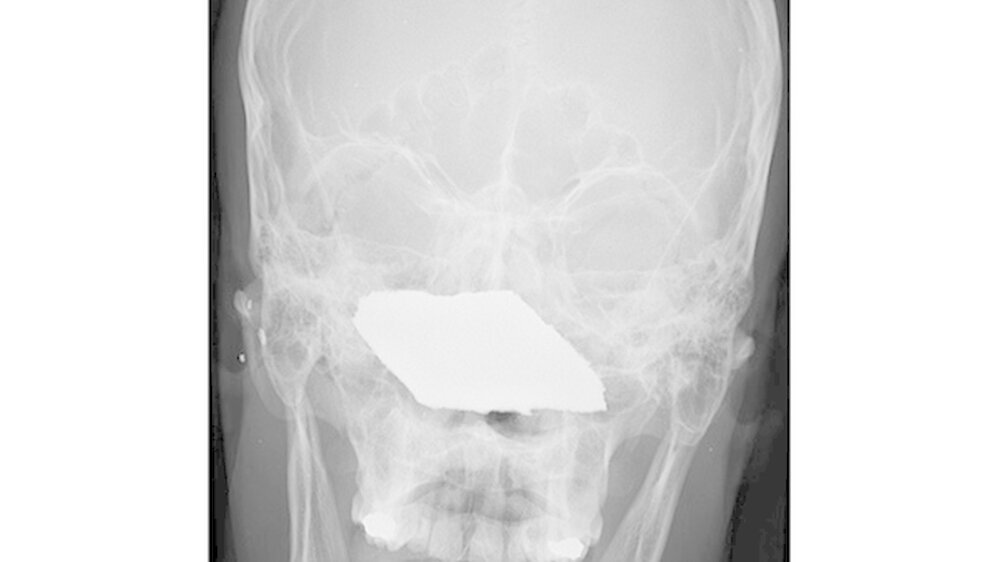

Vom Bohrer im Kopf bis zum Schlüssel in der Kieferhöhle: Die MKG-Chirurgen der Charité haben ausgewählte Patientenfälle mit Fremdkörpern im Gesicht zusammengestellt. In unserer Fotostrecke finden Sie die eindrucksvollen Aufnahmen.